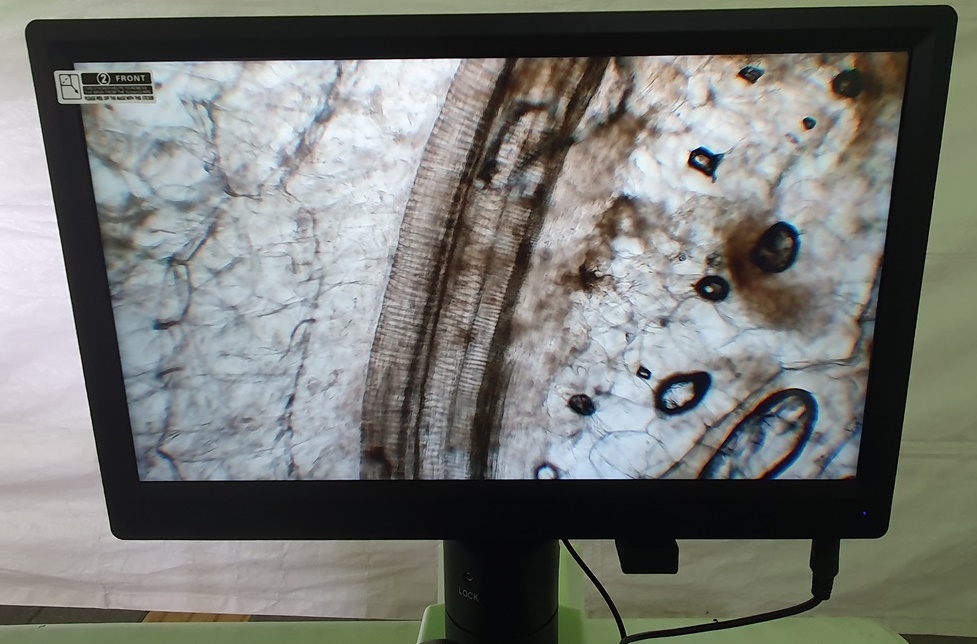

◇ 모세혈관으로 나의 건강 상태 알아보기

9- ▲ 모세혈관으로 나의 건강 상태 알아보기.

10-▲ 아동 혈관 좋음.

11-▲ 성인의 고지혈증

12-▲ 모세혈관의 여러 가지 모습.

손톱 밑에 피부가 시작하는 부위에 투영액을 묻혀서 채혈 없이 모세혈관의 변형, 개수, 혈액의 속도, 세포액의 투명도, 모세혈관 등을 맨눈으로 확인하여 자신의 건강 상태를 파악할 수 있다. 어린 사람은 고지혈증이

없으므로 모세혈관이 10과 같이 반듯하다. 그러나 고지혈증이 심한 어른은 10과 같이 끝이 고불고불하다.